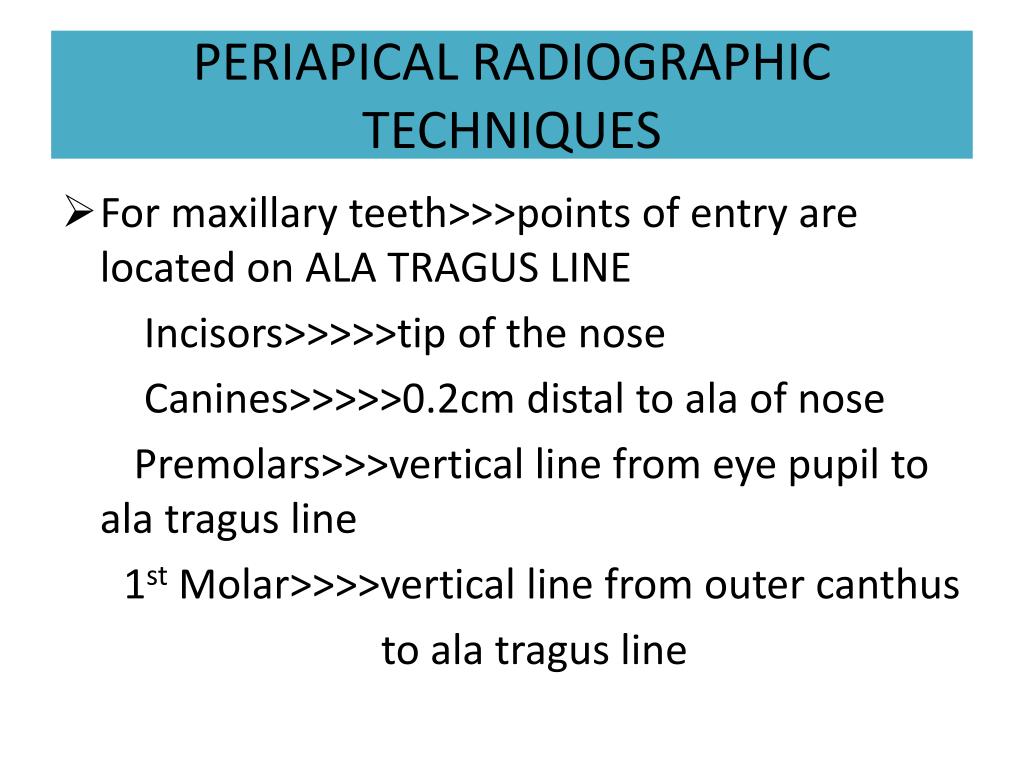

Ala tragus line panoramic. Ikfanson hing university of alabama scho. An imaginary plane or line from the orbital ridge to the acoustic. An imaginary plane or line from the ala of the nose. The roots of the anterior teeth are in the image and the posterior teeth are the same size on each.

This position is often referred to as the patient being positioned with the ala tragus line in a minus 50 position. At the same time this position allows the ala tragus line to be correctly positioned. The panelipse panorex i and panorex ii use the ala tragus line for patient positioning. Notice the panoramic image is divided into 9 areas that make up the 6 zones that you must learn to picture each panoramic radiograph or image in your mind s eye.

Tragus of the ear must be aligned with the plastic guides ala tragus line should be 50 from level positioning the patient position the patient panoramic lead apron must be used position apron high in front to protect the thyroid apron should be lower in back to expose the neck. Discussion most panoramic x ray machines use the ala tragus line for patient positioning whereas a few use the orbito meatal line. Ala tragus line is one of the common extra oral soft tissue land mark utilized in dental clinics for occlusal plane orientation. Here the occlusal plane should be mildly curved upward to make a smile like line.

The ala tragus line as a guide for orientation of the occlusal plane in complete dentures 1carole abi ghosn 2carla zogheib. The smile line will also be lost. An imaginary plane or line from the ala of the nose to the tragus of the ear. The part of a panoramic x ray machine where the cassette is positioned for exposure.

The angle between this line and the horizontal plane is 3on the panorex and 4on the. Focal trough layer that area between the x ray source and the image receptor that will be imaged distinctly on the panoramic. In other words the ala of the nose should be slightly inferior to the height of the tragus. These zones are as follows.

Important in determining the correct position of the patient s head. Exposure was 80 to 90 kv at 10 ma for 1 5 to 2 seconds in accordance with the subject s physical. The panorex i s. To achieve the correct vertical angulation the head must be positioned upright and symmetrical with the ala of the nose just inferior to the height of the tragus.